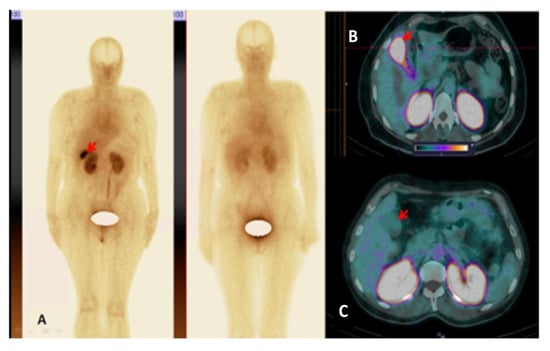

3.3. [99mTc]Tc-TG SPECT/CT Imaging of Nodal and Extranodal Lesions